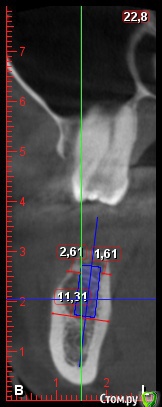

DenisV Опубликовано 22 мая, 2018 Поделиться Опубликовано 22 мая, 2018 Уважаемые коллеги, подскажите советом, допустимо ли с вестибулярной стороны 1.5мм кортикальной кости, или лучше НКР? на фото имплант 4.3*10? Ссылка на комментарий